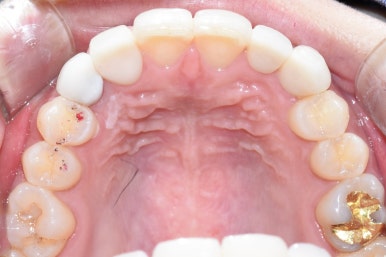

치료 전

위 사진을 보면 환자분이 왜 그런 점들을 고치고 싶으신지 알 수 있습니다.

사진상

왼쪽 송곳니: 임플란트, 오른쪽 송곳니: 색 보완과 고른 배열을 위한 신경치료+크라운

대문니 2개: 고른 배열과, 옥니 보완을 위한 무삭제 라미네이트

대문니 옆 양쪽 치아 2개: 오래된 PFM크라운을 제거하고,

요즘 많이 쓰는 재료인 더 자연스러운 지르코니아크라운

으로 위쪽 앞니(상악 전치) 총 6개의 치료를 들어가게 되었습니다.